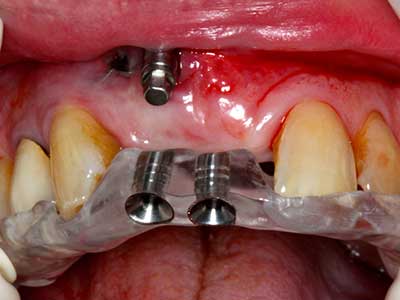

Aplicación: Partición ósea / Cortical Split

El tejido óseo no solo tiene un contenido puramente mineral, sino que también presenta una importante proporción de fibras de colágeno. Esto no solo garantiza una buena resistencia a la presión, sino también una cierta flexibilidad, que puede aprovecharse para la realización de aumentos. En la plastia de expansión clásica a efectos de una partición ósea, la cresta maxilar atrofiada se divide en su eje longitudinal y, tras alcanzar una profundidad de osteotomía suficiente, se extiende con cuidado (fig. 13-16), en un caso ideal sin desperiostizar de forma visible el maxilar (Brugnami, Caiazzo et al. 2014, Stricker, Fleiner et al. 2014). Los sistemas de tornillos y placas con distancia de expansión creciente han demostrado su eficacia para distanciar entre sí las dos tablas óseas por debajo del umbral de rotura. Por regla general, se requieren anchuras de hueso residual de al menos 3 a 4 mm (Chiapasco, Zaniboni et al. 2006) para garantizar una flexibilidad y una cobertura ósea suficientes de los implantes que van a incorporarse. En caso necesario, una osteotomía de descarga vertical unilateral o bilateral puede mejorar la flexibilidad. Como alternativa a la técnica clásica se ha descrito una combinación con otras técnicas de aumento, sobre todo en la parte bucal.

Con el uso de sierras piezoeléctricas la división se efectúa de forma especialmente cuidadosa y sin pérdidas importantes de las dimensiones, por lo que no se han encontrado diferencias significativas entre los implantes realizados en el maxilar dividido y en la cresta alveolar no deficitaria (Chiapasco, Zaniboni et al. 2006, Danza, Guidi et al. 2009). No obstante, precisamente en la partición profunda y limitada de forma local, es preciso asegurarse de que exista una adecuada irrigación por agua para evitar que se produzcan sobrecargas térmicas en las áreas de osteotomía apical.